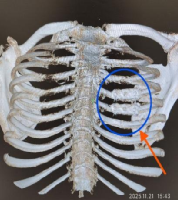

术中胸腔镜下对断裂、错位的肋骨进行了复位及牢固的固定;术后复查肋骨CT见肋骨内固定位置合适、固定牢固(见图五);患者术后伤口恢复良好(见图六),已顺利出院。

图五 图六